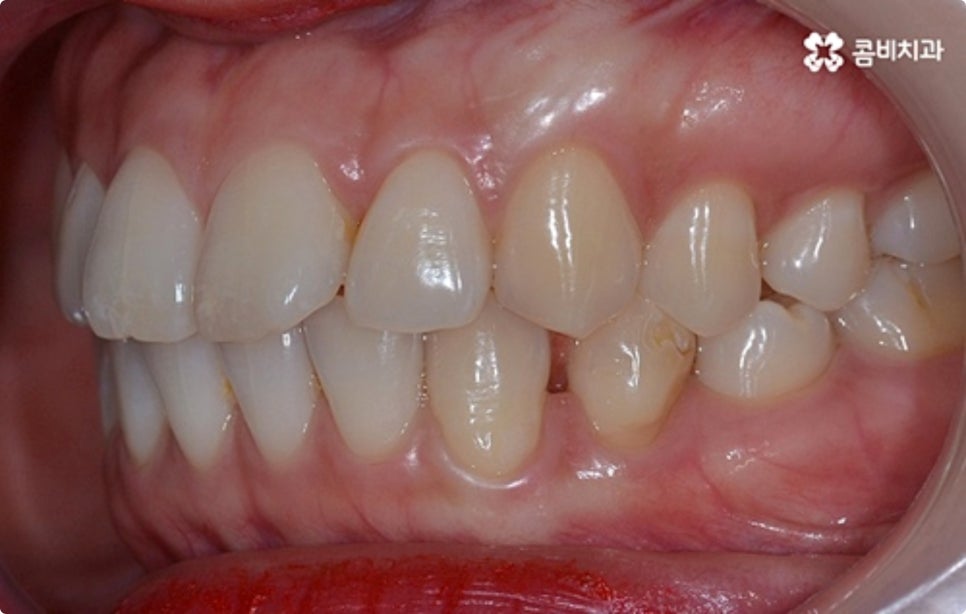

출처 아카이브 열기타인과 대화를 하거나 웃을 때 자연스럽게 보이는 치아는 첫인상에 큰 영향을 주기 때문에 심미적으로 굉장히 중요하다고 볼 수 있습니다. 희고 고른 치열을 가지고 있다면 단정하고 호감가는 인상을 주는 반면 비뚤어진 치열을 가지고 있으면 자신도 모르게 위축이 되어 웃을 때 손으로 입을 가리게 되는 등 콤플렉스가 생길 수도 있는데요.

그렇기 때문에 특히 업무상 대인 관계가 활발한 분들의 경우 직장인치아교정 을 고려하시는 분들이 많이 있어요. 심미적인 이유 때문 만이 아니라 돌출입, 주걱턱 등 부정교합 증상으로 불편함을 겪고 있다면 기능적으로도 문제가 될 수 있으며 이는 시간이 지날수록 악화될 가능성이 있으니 될 수 있는대로 빨리 직장인치아교정 을 통해 바로 잡는 것이 구강 건강을 위해서도 좋을 거예요.

클리피씨 교정도 치아 색상의 세라믹 재질을 사용하기 때문에 심미성이 높은 편이지만 만약에 장치가 아예 겉으로 드러나지 않았으면 좋겠다고 생각하신다면 브라켓을 치아 안쪽에 부착하는 설측교정을 이용할 수 있는데요. 하지만 설측교정은 혀와 맞닿는 부분의 이물감, 통증, 발음상 문제 등을 일으킬 수 있기 때문에 잘 보이는 윗니는 설측으로, 잘 드러나지 않는 아랫니는 보통 교정과 같이 순측 (입술쪽) 으로 진행하는 콤비교정을 통해 이를 보완할 수 있어요. 사진에서 살펴보실 수 있는 케이스 역시 이렇게 콤비로 진행한 직장인치아교정 과정으로 시간이 지날수록 점차 치열이 가지런해지고 교합이 올바르게 개선되는 것을 확인해 보실 수 있습니다.